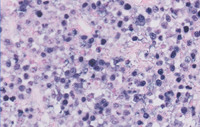

Figure 4: Touch Preperation in Plasmacytoma-Like PTLD, EBV+

Touch preparations demonstrate scattered plasma cells within the lesion.